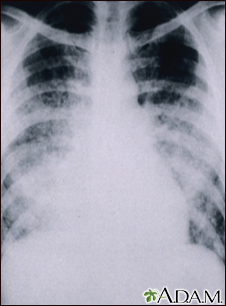

Chickenpox, acute pneumonia - chest x-rayBackChickenpox, acute pneumonia - chest x-rayThis chest x-ray shows cloudiness throughout the lungs, caused by acute pneumonia following chickenpox. Pneumonia, as a complication of chickenpox, rarely occurs in children, but occurs in about one-fifth of adults. E-mail FormEmail ResultsName:Email address:Recipients Name:Recipients address:Message: